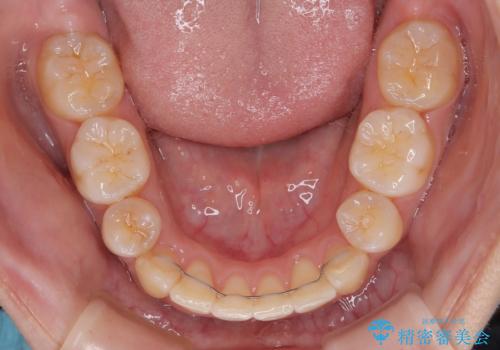

- メタルブラケット

- 3年3ヶ月

上下の前歯が接触する仕上がりとなったので、横顔の印象が大幅に改善されました。